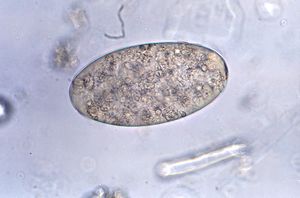

المتوارقة البوسكية إنگليزية: Fasciolopsis buski يطلق عليها عموما ديدان الأمعاء العملاقة